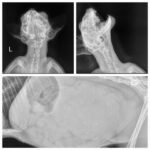

Der kleine Kater kämpft wie ein Löwe. Er will leben. Die Flüssigkeit im Bauchraum wird im Rekordtempo weniger. Der Bauchunfang nimmt ab und man spürt jeden Knochen dieses zarten Kätzchens. Er ist so müde…

Sein Zustand nach wie vor kritisch. Kätzchen in dem Zustand sind Intensivpatienten.

Die gelbfärbung der Ohren verringert sich. Gelb wird zu weiß. Er ist so blass. Er bekommt Flüssigkeit und muss gefüttert werden. Alleine essen möchte er noch nicht.